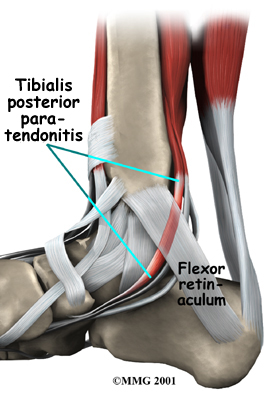

Problems with the posterior tibial tendon seem to occur in stages. Initially, irritation of the outer covering of the tendon, called the paratenon, causes paratendonitis. This means that there is inflammation between the lining of the tendon and the tendon itself where it runs through the tunnel behind the medial malleolus. This tendonitis can start a process of wear and tear on the tendon fibers.

As the tendon heals itself from wear and tear, scar tissue forms, thickening the tendon. This process can continue to the extent that a nodule, or knot, forms within the tendon. Once the painful tendon has changed in structure, the term tendonosis, rather than tendonitis, is used. Unlike with tendonitis, recent evidence shows that inflammation is not present with tendonosis. The area of structural change in the tendon is weaker than normal tendon. The weakened tendon sets the stage for the possibility of rupture of the tendon.